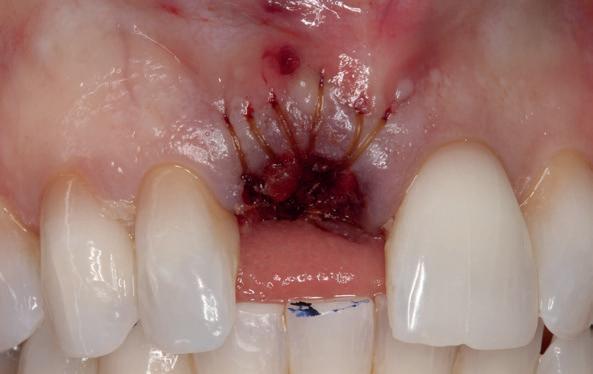

Implantologische behandelingen in het esthetische front vragen meer dan technische vaardigheid alleen. Ze vragen om overzicht, timing, vertrouwen en een team dat als vanzelf samenwerkt onder druk. Juist bij complexe casussen, waarin angst, infectie en hoge esthetische verwachtingen samenkomen, wordt zichtbaar hoe bepalend de rol van de tandartsassistent is.

Deze casus beschrijft een uitgebreide immediate implantaatbehandeling bij een patiënt die door meerdere collega’s werd geweigerd. Niet omdat de mogelijkheden ontbraken, maar omdat de complexiteit vroeg om een perfect afgestemde samenwerking. Het verhaal laat zien hoe de assistent in zo’n traject veel meer is dan een uitvoerende kracht of “mal”, maar een dynamische surgical guide die het proces mede stuurt, bewaakt en mogelijk maakt.De patiënt: wanneer alles samenkomt

Ze kwam binnen op een dinsdagochtend, iets voor achten. Een vrouw van begin zeventig, met een zachte stem en ogen die meer vertelden dan haar woorden. Ze vertelde dat ze een eigen B&B had en dat ze zich nauwelijks kon voorstellen gasten te ontvangen zonder tanden. Op dit moment kon ze echter nauwelijks lachen. “Het doet pijn… en het ruikt soms ook niet goed,” zei ze bijna verontschuldigend. Haar oude bovenbrug, die ze al meer dan twintig jaar droeg, was langzaam maar zeker ingestort. Er was sprake van cariës onder meerdere pijlers, pusafvloed,

chronische ontsteking en een brug die mobiel was en elke beet pijnlijk maakte. Ze had inmiddels meerdere tandartsen bezocht. Drie hadden haar geweigerd. Te complex. Te veel wensen. Te onvoorspelbaar.

De kern van haar vraag was eenvoudig en tegelijkertijd uitdagend: Is het mogelijk om mijn huidige brug te dupliceren en een nieuwe brug te vervaardigen met minder complicaties?

De basis van een complexe beslissing

Mijn behandelplan begint altijd met een uitgebreid klinisch onderzoek. Dat omvat een medische anamnese, intra- en extra-orale camerafoto’s en uitgebreid verwachtingsmanagement. In deze fase is mijn assistent vooral bezig met het zorgvuldig vastleggen van alle gegevens. Juist dat nauwkeurig documenteren zorgt voor rust in de behandelkamer. Minstens zo belangrijk is het luisteren naar de patiënt. Niet alleen naar de klachten, maar naar het

levensverhaal en de mens achter de brug. Begrijpen wat deze behandeling voor iemand betekent, is cruciaal voor het uiteindelijke succes.

Na het klinische onderzoek volgde het röntgenologisch traject. De CBCT liet precies zien wat we al vreesden: een front waarin het bot onregelmatig was, duidelijke radiolucenties rond de pijlers en een infectiegebied dat zich onder vrijwel de gehele brug had verspreid. Tegelijkertijd was er ook potentie. Net voldoende botstructuur om immediate implantaatplaatsing te overwegen, mits alles perfect gepland zou worden.